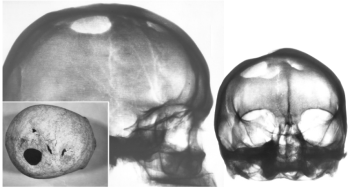

102. ábra. Többszörös trepanáció a falcsonton és homlokcsonton. A legnagyobb csonthiány szövődménymentesen, a kisebbek (amint ez a rtg képeken is jól látszik) osteomyelitises csontfelrakódással gyógyultak. 10–11. század, adultus férfi

Korábban 446 koponyán 15 esetben (3,4 %) találtunk sérülést és/vagy trepanációt (Pap és Józsa 1991). A négy nyílt koponyasérülés közül egyben, a négy lékelésből szintén egyben mutattunk ki fertőzéses szövődményt (102. ábra). Hasonló arányú szeptikus szövődményről számolnak be mások is (Bakay 1985, Bartucz 1966, Marino és mtsa 2000, Rifkinson-Man 1988). A 10–12. századi sebészek jó higiénés körülmények között, kevés vérveszteséggel, csekély szöveti roncsolással, a sérült csontrészeket gondosan eltávolítva végezték műtéteiket. A koponyalékeltek több mint kétharmada felgyógyult, sorsuk természetesen nemcsak a műtéti technikától, esetleges szövődményektől, hanem elsősorban a műtétet indokoló sérüléstől függött. A hazai leleteknek mindössze egyhetede a befejezetlen trapanáció, hasonlóan egyes dél-amerikai területek magas gyógyulási arányához. Anda (1951) számításai szerint a trepanáltak 69%-a több mint három hónappal túlélte a műtétet. Marino és mtsai (2000) a preinka és inka-kori lékelések tartós túlélési rátáját 70%-nak találták. Összehasonlításul néhány adat: a Nagy-Britanniában a trepanált koponyák 6%-ában (Parker és mtsai 1986), a 19. századi hazai anyag (Bartucz 1966) 10%-ban észleltek túlélést. Ezeknek ismeretében lehet igazán csodálni a 10–12. századi magyar gyógyítók műtéti eredményeit, amint Anda (1951) megjegyezte: „...a honfoglaló magyarok a korabeli orvosi ismereteket jóval meghaladó tudás birtokában voltak [ ] fejlett trepanációs ismeretekkel rendelkeztek”.